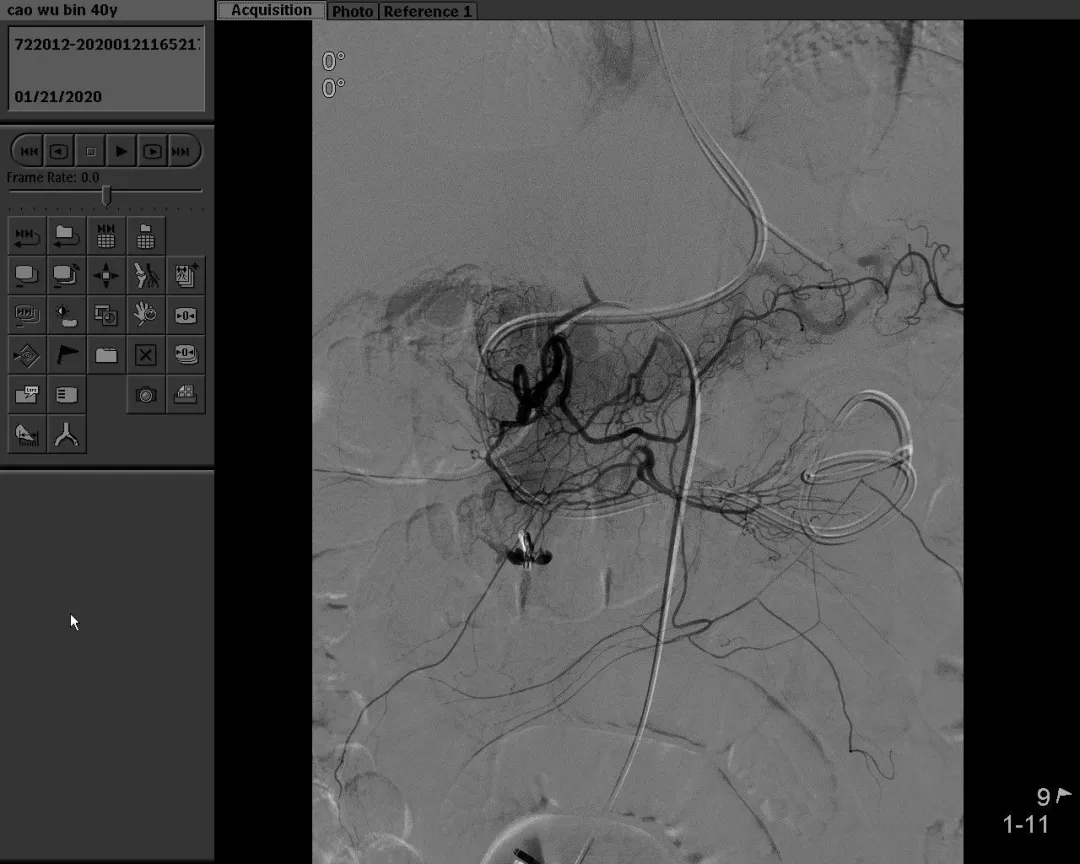

病例三:男,解暗红色血便10余天,外院胃肠镜无明显出血灶,以“消化道出血”收治住院。

急诊DSA示:空肠动脉分支出血,予空肠动脉栓塞术。